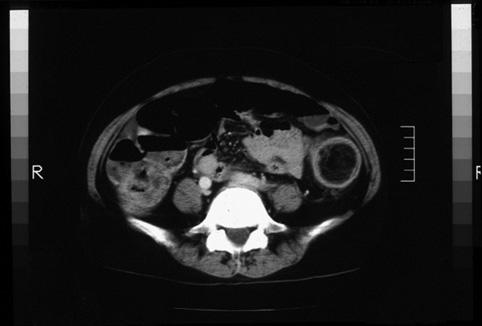

장중적과 주변부에 수반성의 궤양을 동반한 결장의 지방종

[Image-ID:9367]

대장/하행

CT

35~40